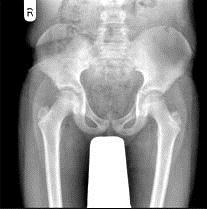

男,请根据其正常骨盆影像图像,判断其最可能的年龄 ( )A、20岁左右B、25岁左右C、10岁左右D、15左右E、5岁左右

问题 男,请根据其正常骨盆影像图像,判断其最可能的年龄 ( )

选项 A、20岁左右 B、25岁左右 C、10岁左右 D、15左右 E、5岁左右

答案 C